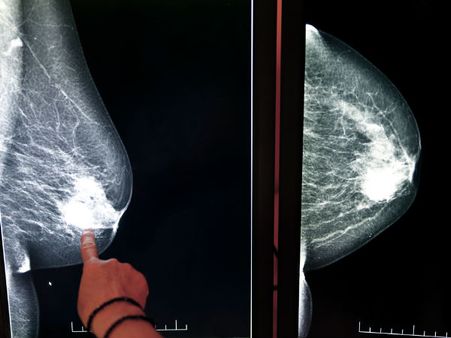

9 Effective Ways To Prevent The Risk Of Breast Cancer

Worldwide, breast cancer is the most common cancer in women. It occurs when there is an abnormal growth of breast cancer cells that divide at a faster rate and start accumulating to form a lump in the breast. In this article, we will write about the ways that may reduce the risk of breast cancer.

9. Undergo screening every month

Undergoing breast cancer screening can help in early detection of breast cancer. Screenings can aid in preventing the early stages of breast cancer which makes it easier to treat it.